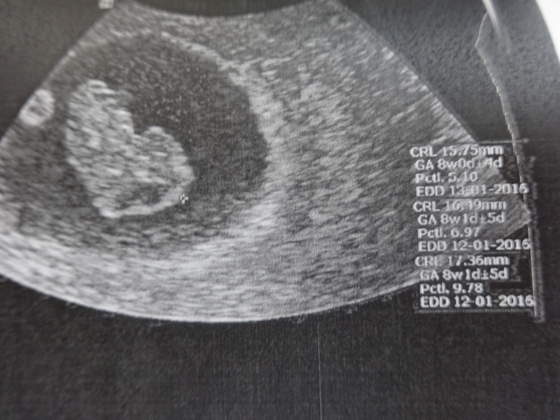

ALe Fasol jest super, śliczny, równo o 2 tygodnie urósł, czyli jak powinien. Wyniki badań też w porządku i ogólnie dobrze. Kolejna wizyta 23 czerwca i już na NFZ, uff odciąży to trochę mój portfel

A Fasolek wygląda już powoli jak człowieczek, ma rączki i nóżki. Na USG super to wyglądało

A to mój Fasolek, wymiary chyba widać na zdjęciach

Na tym pierwszym widac skulonego człowieczkami, widzicie?